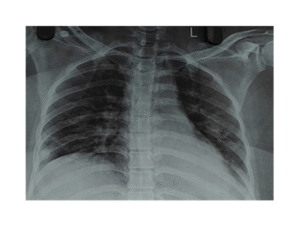

Management of Severe Viral Pneumonia with Type-1 Respiratory Failure and ARDS in a 33-Year-Old Female: A Case Report InJPharPract, Vol 19/Issue 2/2026 InJPharPract, Vol 19/Issue 2/2026 | Management of Severe Viral Pneumonia with Type-1 Respiratory Failure and ARDS in a 33-Year-Old Female: A Case Report DOI:10.5530/ijopp.20250461Read More